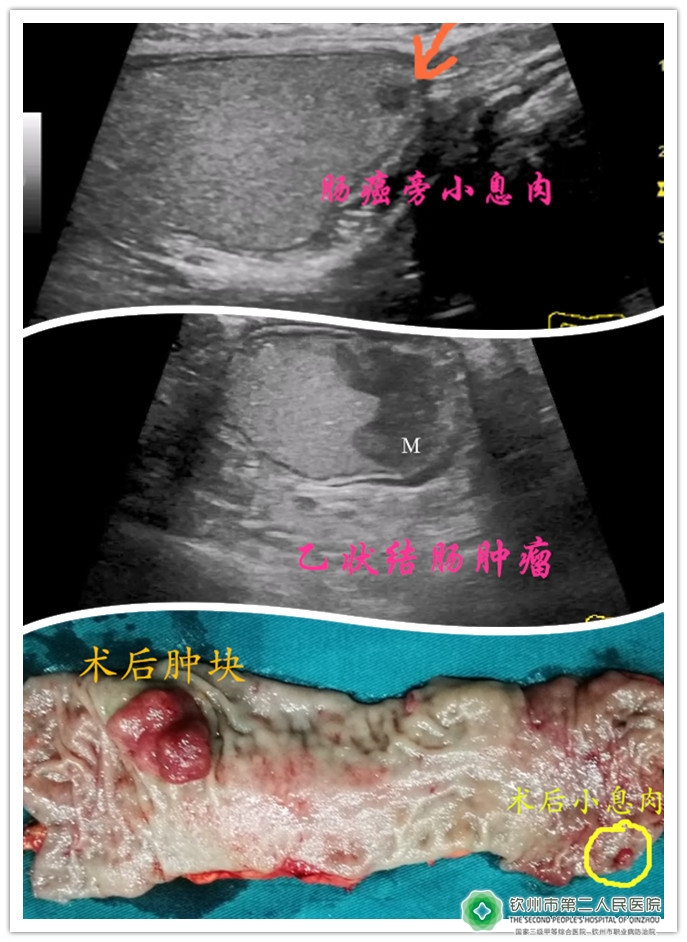

(乙状结肠肿瘤)